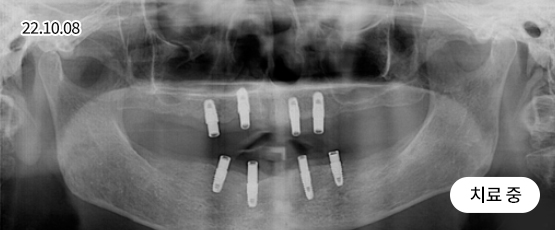

임플란트 틀니

임플란트 틀니는 훨씬 더 안정적이고 튼튼합니다.

임플란트 틀니는 상위(위 턱) 4개, 하악(아래 턱) 4개의 임플란트 뿌리를 식립하고

자석형 틀니를 고정함으로써 다수의 치아를 수복하는 치료방법입니다.

• 상악(위 턱)과 하악(아래 턱)에 틀니 고정을 위한 임플란트 뿌리를 식립

• 틀니 고정장치(자석형)를 구강에 시적, 교합과 안정을 맞추는 과정